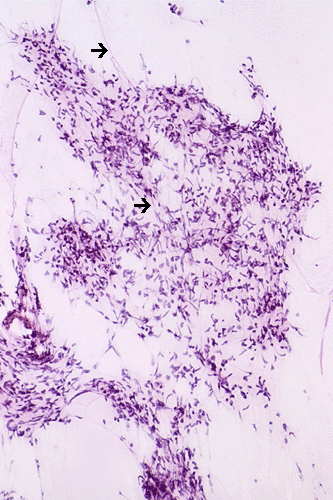

The lesional cells occur in clusters and with elongated cytoplasmic processes (Ú). The nuclei are hyperchromatic and somewhat angulated resembling a "baking potato". They tend to lie in parellel with the axis of their elongated cytoplasm. Nucleoli are not seen.